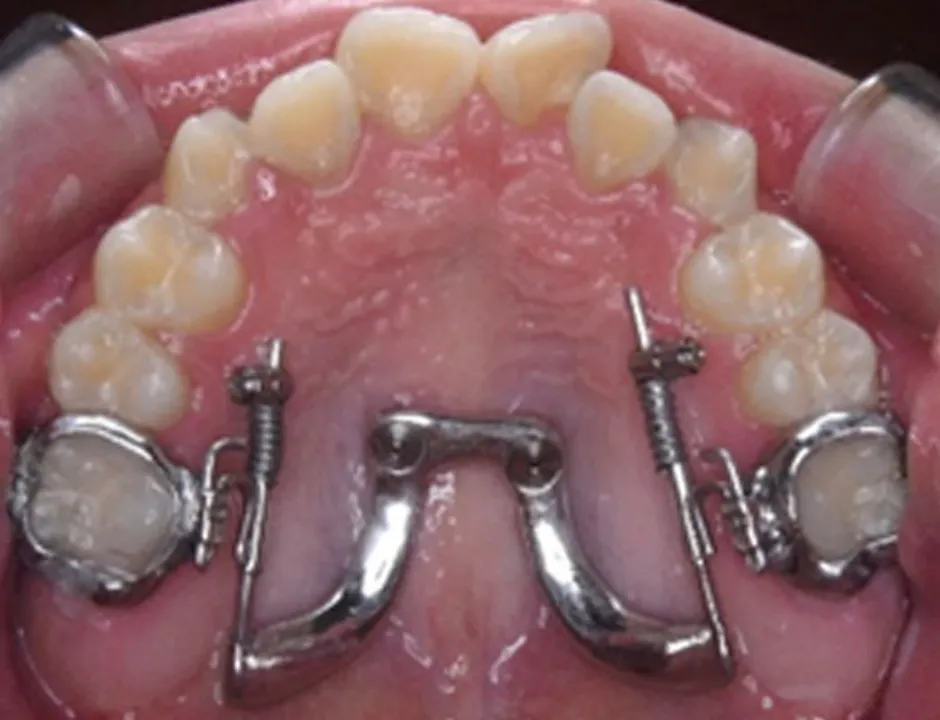

MSE(上顎骨骨格性拡大装置)は、矯正用アンカースクリューを使って上顎の骨を横に拡大する装置です。上顎の骨は左右に分かれており、その真ん中に正中口蓋縫合とよばれる骨のつなぎ目があります。MSEは、この骨のつなぎ目の右と左にそれぞれ2本ずつ、計4本のアンカースクリューを埋め込んで固定します。これによって左右の骨が少しずつ引き離され、その間に新しい骨が形成されることで、上顎の骨を横へと拡大できます。

体への負担を軽減できる

具体的には、3Dスキャナーを使用して、アンカースクリューのヘッド部、上顎の天井の粘膜、歯の3次元的な位置関係をデータとして取得し、そのデータを基にCAD/CAM技術を駆使して矯正装置を設計・製作します。この3Dメタルプリント矯正装置は、歯への適合性と強度に優れており、幅広い症例に対応が可能です。

デジタル技術の進歩により、現在では3Dスキャナーで取得した患者様の口内の3Dデータを基に、CAD/CAM技術を活用して矯正装置の設計から作製まで行なうことが可能です。矯正用アンカースクリューと連結できる矯正装置も、3Dメタルプリント技術を用いて、患者様一人ひとりに合わせて精密に設計・製作することにより、対応可能な症例の幅が広がっています。